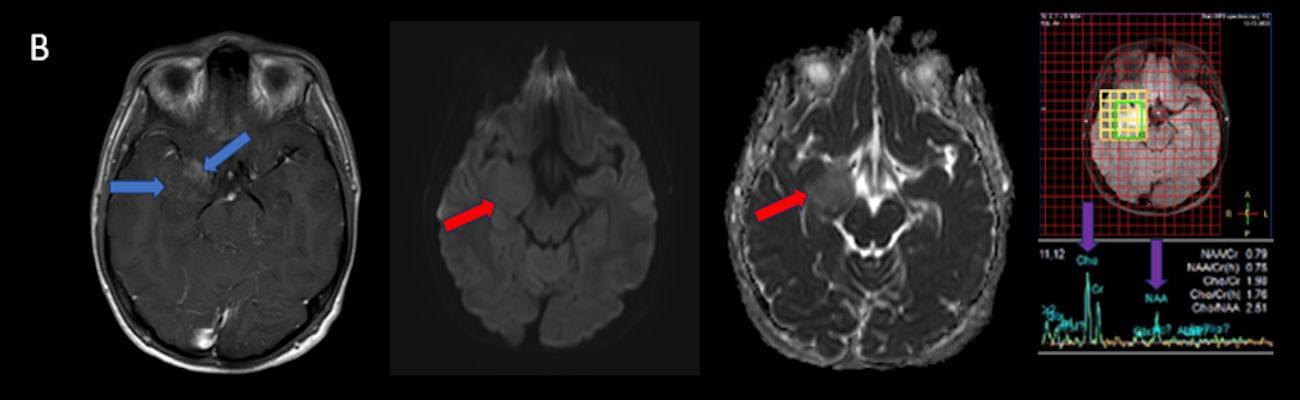

- B) Lezyon difüzyon görüntüde izo-hiperintens, ADC haritalamada hafif hiperintens izlenmiş olup (oklar) diffüzyon kısıtlılığı göstermemektedir. Lezyonun anterior kesiminde kontrastlı serilerde yamalı kontrast tutulumları (oklar) mevcuttur. MR spektroskopide lezyon düzeyinden elde olunan multivoksel görüntülerde kolin pikinde artış ve NAA da azalma (oklar) dikkati çekmektedir. Kolin/kreatinin oranı 1.76 olarak ölçülmüştür.

- MRG: T1A serilerde solid komponent izo-hipointens, T2A serilerde genellikle hiperintens sinyalde görülür. Peritümöral T2/FLAIR hiperintens kitle ödemi oldukça nadirdir. T1 C+ görüntülerde solid komponentte değişken oranda kontrastlanma ,T2*(SWI) serilerde eğer kalsifikasyon eşlik etmekteyse buna bağlı blooming artefaktları görülebilir.